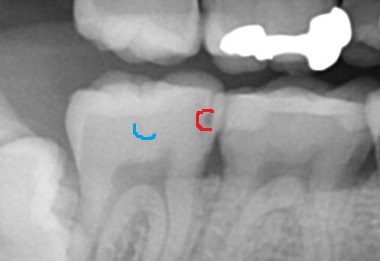

エックス線(レントゲン)写真で歯の内部を確認してみましょう。

エックス線写真では見えない歯の内部が確認できます。

どこに虫歯があるかというと、

赤いところが黒くなっており、虫歯で歯が溶けた像がでています。

青いところも、よくよく見ると、うっすら影があり、こちらも虫歯です。歯の側面ですね。

表面上では黒い線に目が行ってしまいますが、実際に虫歯があるのは歯と歯の間のところです。